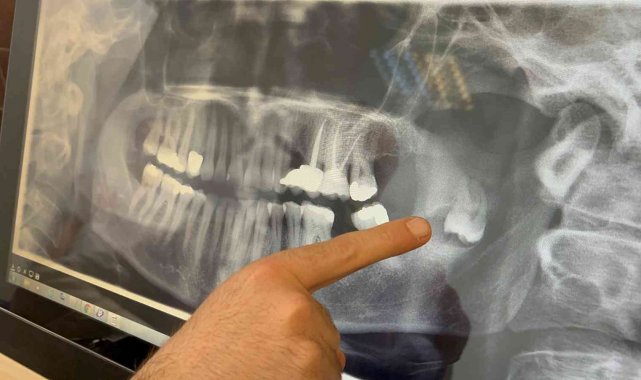

Eskişehir'de yaşayan Sevan Kazak Ertural, yıllar önce fark edilen ve başta zararsız olduğu düşünülen gömülü dişinin kistleştiğini görünce birçok hastaneye başvurdu. Çenesinin ramus bölgesinin derinlerine ilerleyen ters dönmüş haldeki dişin alınması için görüştüğü hekimlerden olumsuz yanıt alan Ertural, sinirlere yakın olmasından dolayı muhtemel bir operasyonun oldukça riskli olduğunu öğrendi. Sonrasında ESOGÜ Diş Hekimliği Fakültesi'ne başvuran Ertural, burada Doç. Dr. Ömür Dereci önderliğinde genel anestezi ile gerçekleştirilen operasyon sonucunda kısa sürede sağlığına kavuştu.

Sevan Kazak Ertural, yaklaşık 12 yıl önce bir panoramik röntgende fark ettikleri gömülü dişin çene kemiğindeki ramus bölgesinde yer aldığını söyledi. Bir zararı olmadığı ve riskli bölgede olduğu için bu dişi almaya kimsenin yanaşmadığını belirten Ertural, "Daha sonrasında dişin kistleştiğini ve çene kemiğime zarar verdiğini fark ettik. Çene kemiğimin bir kısmını eritmişti. Tekrar yaptığım başvurularımda kalıcı yüz felci olabileceğini, çenemin kırılabileceğini, sinire çok yakın olduğu için kolayca müdahale edilemeyeceğini söylediler. Bu sene içinde Ömür Hoca ile tanıştım, buraya başvurdum. Sağ olsun beni çok cesaretlendirdi, bütün riskleri anlattı. Korkmamam gerektiğini söyledi ve ondan güven alarak burada ameliyat olmaya karar verdim" dedi.

Süreç hakkında bilgi veren Doç. Dr. Ömür Dereci, hastanın yaklaşık birkaç ay önce çenesinde ciddi bir ağrı şikâyetiyle kliniğe başvurduğunu kaydetti. Doç. Dr. Dereci, "Yapılan incelemelerde çenesinde tamamen pozisyonu bozuk, ters dönmüş ve yukarı doğru çenenin derin taraflarına doğru ilerlemiş bir diş ve bu dişle ilişkili bir kiste rastladık. Cerrahi bir operasyonla hastamız tamamen uyutularak ameliyat edildi ve bu diş ve ilişkili kist buradan tamamen çıkarıldı. Yapılan muayene ve kontrollerde gayet iyi iyileştiği gözlendi" diye anlattı.